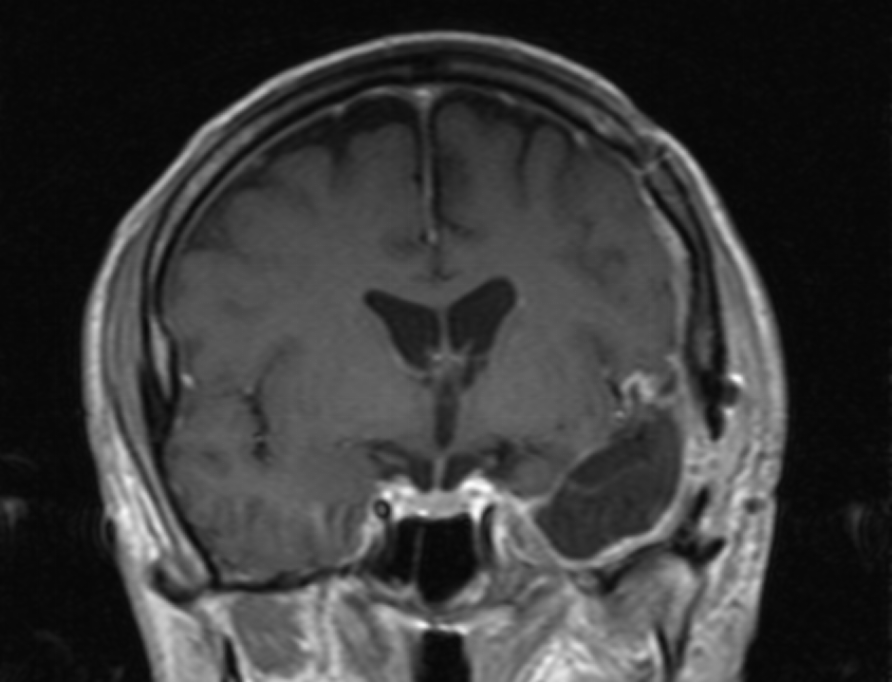

Το δόγμα της σύγχρονης χειρουργικής όγκων απεικονίζεται στις μαγνητικές αυτές. Στόχος μας είναι η μέγιστη δυνατή ασφαλής αφαίρεση του όγκου. Δεν πρέπει να στοχεύουμε στην εξαίρεση όχι μόνο του όγκου, όπως φαίνεται στην μαγνητική αλλά και στην αφαίρεση και της διηθητικής ζώνης και της υγιούς περιβάλλουσας περιοχής αν αυτή δεν έχει λειτουργίες. Η εικόνα 1α είναι προεγχειρητική, εδώ έχει σχεδιασθεί το εύρος της στοχευμένης εξαίρεσης. Η εικόνα 1β δείχνει το μετεγχειρητικό αποτέλεσμα μιας υπερολικής εξαίρεσης. Πρόκειται για την πρώτη ασθενή που χειρουργήθηκε στην Ελλάδα από τον Καθ. Γούσια τον Οκτώβριο του 2023, η οποία διαγνώσθηκε με την πιο επιθετική μορφή του γλοιοβλαστώματος, το λεγόμενο γλοιοσάρκωμα, η οποία 20 μήνες μετά την χειρουργική επέμβαση παραμένει χωρίς ένδειξη όγκου στην μαγνητική και το πιο σημαντικό χωρίς νευρολογικά ελλείμματα.